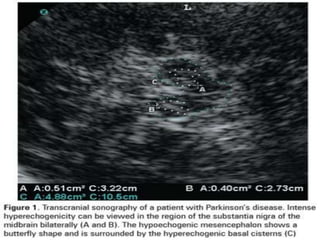

•IMAGINGFOR

PARKINSON’S DISEASE